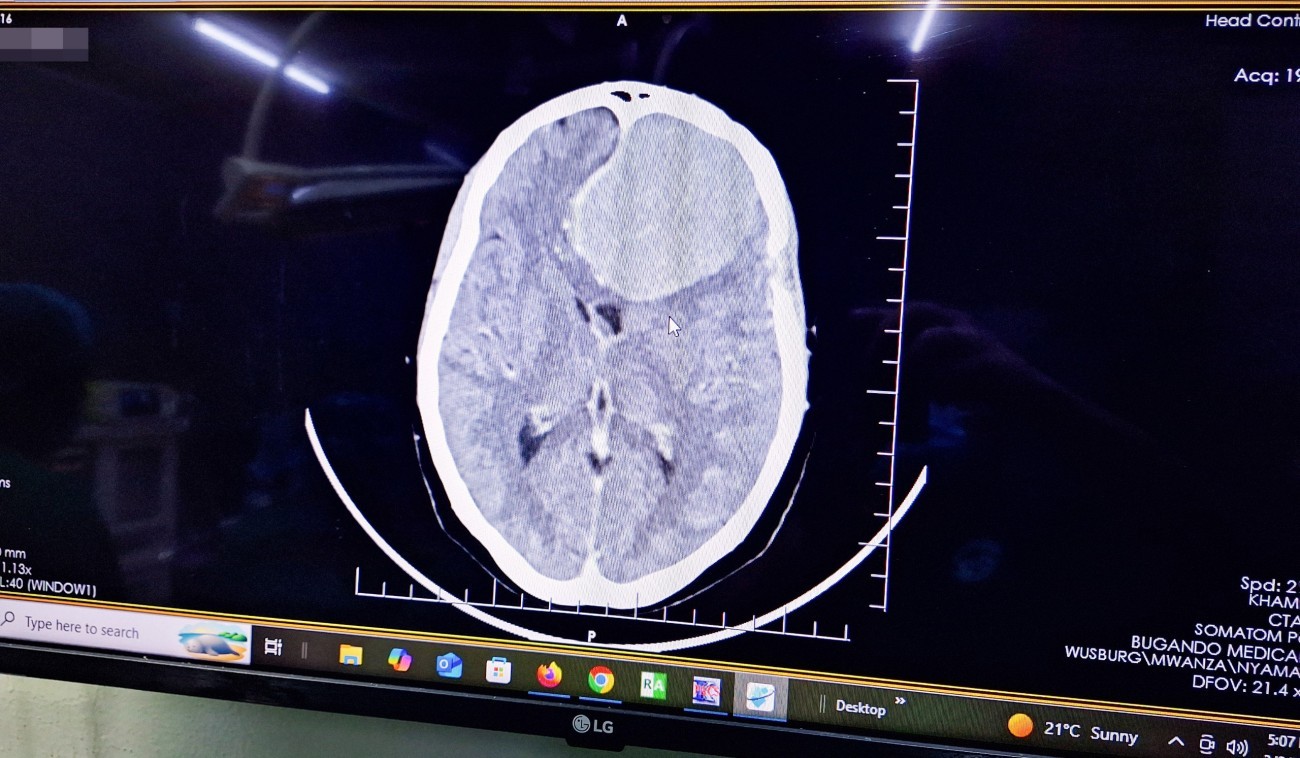

Der erneute humanitäre Einsatz eines neurochirurgischen Teams der Medizinischen Universität Lausitz – Carl Thiem (MUL – CT) in Tansania ist erfolgreich gestartet. „Am ersten Tag konnten insgesamt fünf Operationen durchgeführt werden, darunter vier große Hirntumoroperationen, eine davon bei einem sechsjährigen Kind“, berichtet Prof. Dr. med. Ehab Shiban, Chefarzt der Neurochirurgischen Klinik der MUL – CT. Alle Patientinnen und Patienten seien wohlauf.

Bereits im Jahr 2025 hatte die MUL – CT einen ersten erfolgreichen Einsatz am BMC realisiert. Damals standen hochkomplexe Eingriffe bei bösartigen sowie außergewöhnlich großen Hirntumoren im Fokus. Aufbauend auf diesen Erfahrungen wurde das medizinische Konzept nun gezielt weiterentwickelt: Im Mittelpunkt der aktuellen Einsatzwoche stehen gutartige Tumore, insbesondere sogenannte Meningeome.